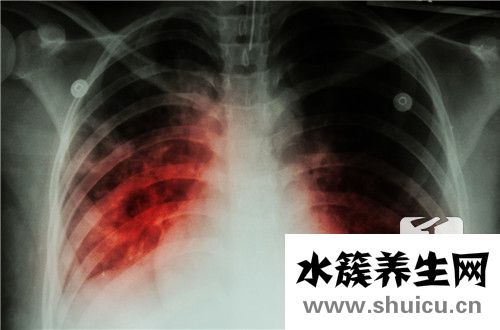

許多人經常患上結核病。 關鍵與人體抵抗力差有關。 一旦患有結核病,人體的抵抗力將繼續惡化。 由于患者的飲食將變得越來越異常,因此大多數患者的食欲將大大降低。 因此,如果兒童患上結核病,他們所有...